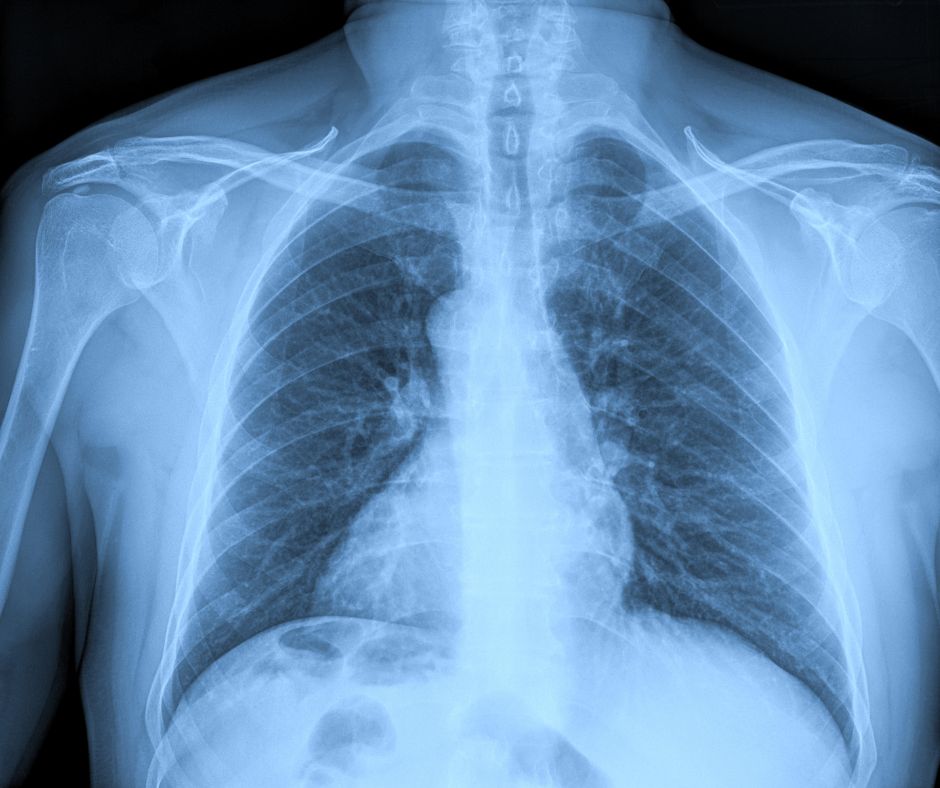

- Imaging tests: Diagnostic imaging such as X-rays, MRI’s and Ultrasound are a valuable tool in assessing shoulder conditions.

- X-rays are often the first step, helping to quickly identify fractures, dislocations, and degenerative changes like arthritis. For sports injuries, X-rays are especially useful for detecting acute trauma.